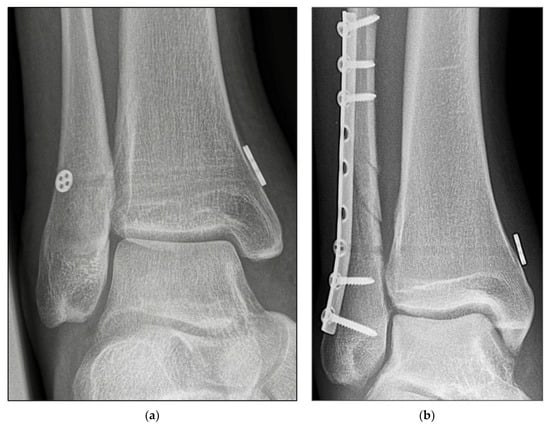

2.3. Surgical Procedure